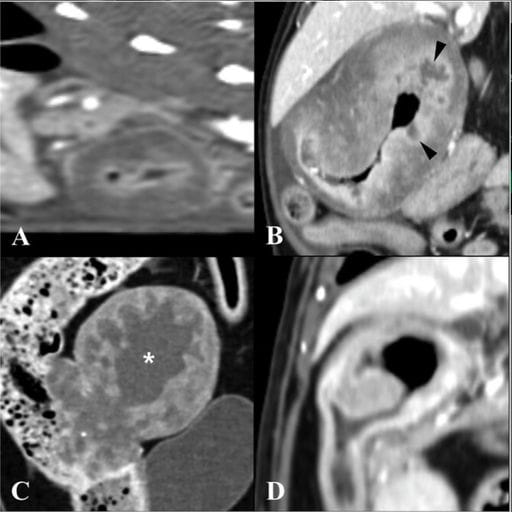

Postcontrast sagittal (A) and dorsal (B–D) CT images demonstrating different lesion shapes in FGESF. (A) Circumferential symmetric lesion at the pyloroduodenal junction (PDJ) showing homogeneous contrast enhancement with mucosal layer enhancement. (B) Circumferential asymmetric endophytic growth in the proximal duodenum showing heterogeneous contrast enhancement. Ulcerated regions are indicated (black arrowheads). (C) Noncircumferential exophytic growth in the descending colon, showing heterogeneous enhancement with a cavitated region (white asterisk). (D) Noncircumferential endophytic growth in the proximal duodenum. CT, computed tomography; FGESF, feline gastrointestinal eosinophilic sclerosing fibroplasia.

FGESF primarily affected young to middle-aged cats (median 3.5 years). Most lesions were gastrointestinal (14/16), frequently involving the proximal duodenum, jejunum, and pyloric regions. Growth pattern correlated significantly with location: proximal duodenum and pylorus consistently showed endophytic expansion. CT commonly revealed heterogeneous contrast enhancement (86%), mucosal layer enhancement (86%), and ulceration (50%). Ultrasonography consistently demonstrated intraparenchymal hyperechoic foci (100%), heterogeneous echotexture (93%), and mixed echogenicity (93%), with loss or alteration of wall layering in all cases. Marked lymphadenopathy occurred in 85% of cats, occasionally showing cavitation. Gastrointestinal perforation was identified in two cats, both of which died within 24 hours postoperatively.

CT and ultrasonography reveal characteristic yet variable imaging features of FGESF. Endophytic growth in the proximal duodenum and pylorus may aid differential diagnosis. Frequent findings include heterogeneous enhancement, mucosal enhancement, ulceration, mixed echogenicity, and hyperechoic intralesional foci. Marked lymphadenopathy is common, and cavitary nodes may reflect FGESF infiltration. Perforation, while rare, portends grave prognosis. The study supports including FGESF among differentials for feline gastrointestinal masses and highlights the diagnostic utility of combining CT and ultrasonography, while emphasizing the ongoing need for histopathological confirmation.